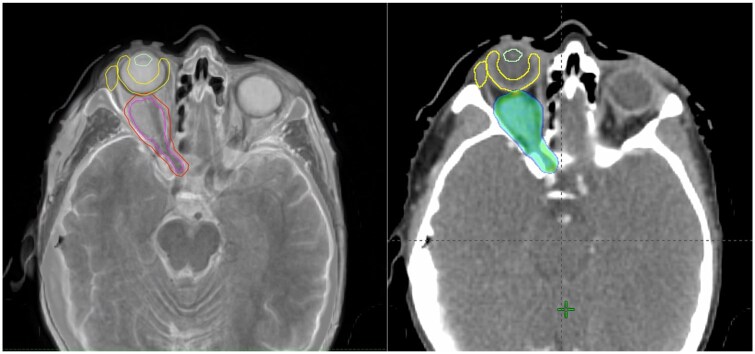

Methods: A retrospective interventional cohort study. Gross target volume included the radiologically evident tumour and the optic nerve (excluded in case of haemangioma). Dosimetry was compared between HA and volumetric modulated arc therapy (VMAT) radiotherapy. Patients were treated with HA and followed-up clinically and radiologically for response and toxicity assessment.

Results: Eight patients were included in our study, six patients with an optic nerve sheath meningioma, one cavernous haemangioma and one orbital schwannoma. All patients demonstrated tumour regression, mean tumour volume prior to treatment of was 4916 mm3 and reduced to 3239 mm3 (P = .03). Three of eight patients showed improvement of visual acuity, three retained excellent pre-treatment vision and two patients had a reduction of vision. HA and VMAT planning target volume coverage dosimetry was similar (D95%: 98.7% and 98.6%, P > .05). The dosimetry of the contralateral lens (32.2 vs 69.8 Gy), lacrimal gland (1.7 vs 7.8 Gy), optic nerve (9.0 vs 26.6 Gy), nasal cavity (10.2 vs 20.6 Gy) and ipsilateral temporal lobe (4.9 vs 11.6 Gy) was significantly improved (P < .001) with HA.

Conclusion: This is the first reported clinical application of HA for benign orbital tumours. HA was an effective and well tolerated treatment modality. HA offered better dosimetry for some of the OARs compared to VMAT.